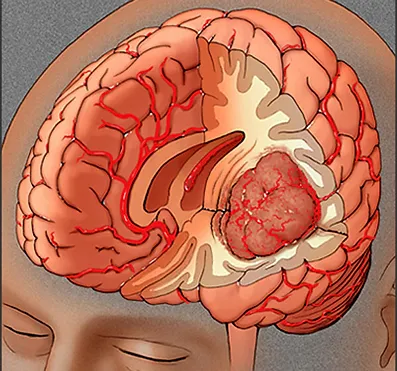

Kötü huylu beyin tümörleri kanser hücreleri içermektedir. Hayatı tehdit ederler. Hızlı büyürler ve etraf normal dokulara yayılarak onların fonksiyon görmesini de engellerler. Genellikle tıpkı ağaçlar gibi etrafa kök salarak beslenmeleri için gerekli olan maddeleri sağlıklı beyin dokusundan çalarak ayakta kalırlar.

Beyin dokusundan kaynaklanan tümörlere birincil (primer) beyin tümörü denilir. İkincil (sekonder) beyin tümörü ise beyin dışı bir kanserin beyne yayılması ile oluşur. Beyin tümörleri kaynak aldıkları dokunun tipine göre adlandırılırlar. En sık görülen birincil beyin tümörü gliomlardır. Bunlar beynin sinir dışı destek hücrelerinden kaynaklanır.